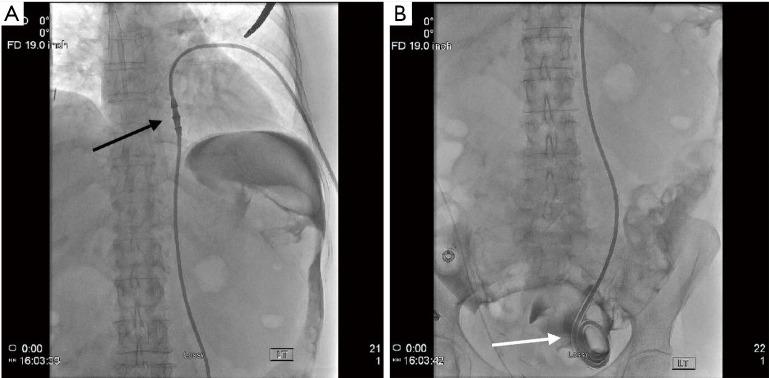

Patients with end-stage renal disease (ESRD) often will ultimately require dialysis to survive. One type of dialysis is peritoneal dialysis (PD), which utilizes the vessel-rich peritoneum as a semi-permeable membrane to filter blood. In order to perform PD, a tunneled catheter must be placed through the abdominal wall and into the peritoneal space, with ideal positioning of the catheter within the most dependent portion of the pelvis, represented by the rectouterine or rectovesical space in women and men, respectively. There are several approaches to PD catheter insertion, including open surgical, laparoscopic surgical, blind percutaneous, and image-guided with the use of fluoroscopy techniques. Interventional radiology (through the use of image-guided percutaneous techniques) is an infrequently utilized resource to place PD catheters, and offers real-time imaging confirmation of catheter positioning with similar outcomes to more invasive surgical catheter insertion approaches. Although the vast majority of dialysis patients receive hemodialysis instead of peritoneal dialysis in the United States, some countries have moved towards a "Peritoneal Dialysis First" initiative, prioritizing initial PD, as it is less burdensome on healthcare facilities as it can be performed at home. In addition, the outbreak of the COVID-19 pandemic has produced shortages of medical supplies and delays in care delivery worldwide, while simultaneously generating a shift away from in-person medical visits and appointments. This shift may be met with more frequent utilization of imaged-guided PD catheter placement, reserving surgical and laparoscopic placement for complex patients who may require omental periprocedural revisions. This literature review outlines a brief history of PD, the various techniques of PD catheter insertion, patient selection criteria, and new COVID-19 considerations, in anticipation for the increased demand for PD in the United States.

终末期肾病(ESRD)患者往往最终需要透析才能存活。一种透析方式是腹膜透析(PD),它利用血管丰富的腹膜作为半透膜来过滤血液。为了进行腹膜透析,必须将一根隧道式导管经腹壁置入腹膜腔,导管的理想位置在骨盆最靠下的部分,在女性为直肠子宫陷凹,在男性为直肠膀胱陷凹。腹膜透析导管插入有几种方法,包括开放手术、腹腔镜手术、盲法经皮插入以及使用荧光透视技术的影像引导插入。介入放射学(通过使用影像引导经皮技术)是一种较少用于放置腹膜透析导管的资源,它能提供导管位置的实时影像确认,其结果与更具侵入性的手术导管插入方法相似。尽管在美国绝大多数透析患者接受的是血液透析而非腹膜透析,但一些国家已转向“优先腹膜透析”倡议,将初始腹膜透析作为优先选择,因为它对医疗机构的负担较小,因为可以在家中进行。此外,新冠疫情的爆发在全球范围内造成了医疗用品短缺和护理交付延迟,同时导致人们减少了面对面的医疗就诊和预约。这种转变可能会使影像引导腹膜透析导管置入的使用更加频繁,而将手术和腹腔镜置入保留给可能需要在围手术期对网膜进行修正的复杂患者。这篇文献综述概述了腹膜透析的简史、腹膜透析导管插入的各种技术、患者选择标准以及新冠疫情的新考量因素,以应对美国对腹膜透析需求的增加。